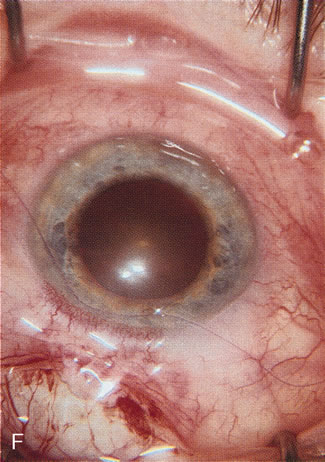

CATARACT EXTRACTION ALONE REDUCES IOP IN MOST EYES WITH ANGLE-CLOSURE GLAUCOMA

Uncomplicated cataract extraction substantially reduces IOP, along with the number of postoperative glaucoma medications in eyes with angle-closure glaucoma.146,147 When preoperative gonioscopy reveals PAS, along with adjacent areas of appositional closure, lens extraction alone in select cases may be a reasonable alternative to filtration surgery.148,149 Phacomorphic angle-closure disease due to enlargement of the lens with progressive angle crowding is eliminated following lens extraction. The width and depth of the anterior chamber angle in eyes with angle-closure glaucoma increases significantly after cataract extraction with IOL implantation and becomes similar to open-angle glaucoma and normal eyes.150,151 (Fig. 5). Combining phacoemulsification, IOL implantation, and limited goniosynechialysis is effective in the treatment of cataract and chronic angle-closure glaucoma.152 Phacoemulsification with implantation of a foldable IOL is more effective in reducing IOP and improving visual acuity than surgical peripheral iridectomy in eyes with acute angle-closure glaucoma.153

Fig. 5. Anterior chamber angle changes associated with lens extraction and PCIOL This 65-year-old Vietnamese woman has a long-standing history of chronic angle-closure glaucoma treated with laser peripheral iridectomy. The optic nerve demonstrated mild glaucomatous damage and IOP was moderately controlled on two antiglaucoma medications. The cataract was removed through temporal clear corneal phacoemulsification with foldable acrylic IOL. A. Symptomatic cataract in narrow-angle glaucoma eye with patent iridectomy. B. Intraoperative goniophotograph showing crowding of angle with increasing narrowness due to phacomorphic component. C. Intraoperative photograph showing temporal clear corneal approach with IOL in the capsular bag. D. Intraoperative goniophotograph demonstrating deepening of chamber angle following lens extraction. Proposed theories for IOP reduction following lens extraction with complete wound closure: